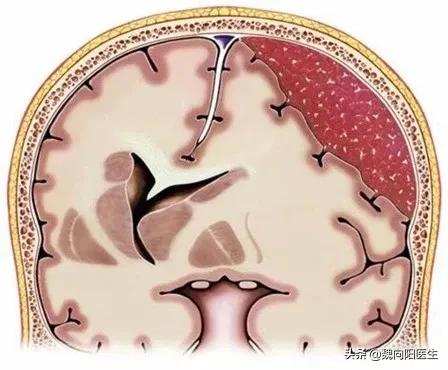

慢性硬膜下血肿 (chronic subdural hematoma,CSDH)是血液集聚在蛛网膜与硬脑膜之间形成的慢性占位性病变,常在头部外伤3周以后形成。

根据血肿部位的不同症状表现也不相似。

表现为记忆力减退、认知功能障碍,甚至痴呆和昏迷。

双下肢无力或者一侧肢体无力。

大小便功能障碍。